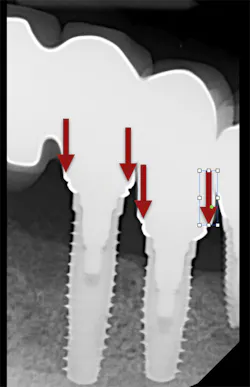

We all know that there are no shades of gray when it comes to the fit of implant-supported restorations—they either fit or they don’t. This makes the accuracy of our impressions especially important when we are fabricating implant-supported restorations. When implant-supported restorations do not fit, the results are increased chair time and appointments, reduced productivity, and increased frustration for both dentists and patients (figure 1).